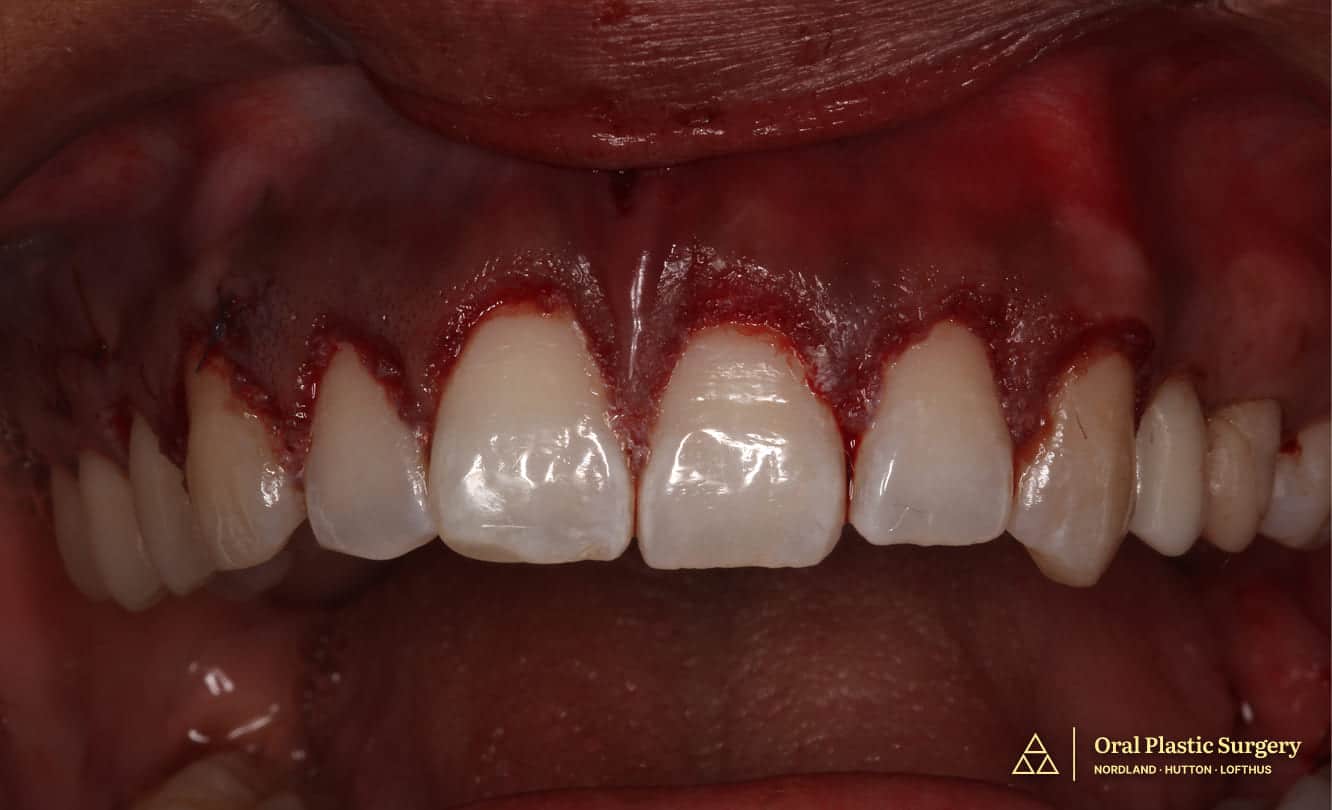

Post connective tissue grafting showing dramatic improvement in root coverage, tissue color, and gingival contour prior to final restorative work.